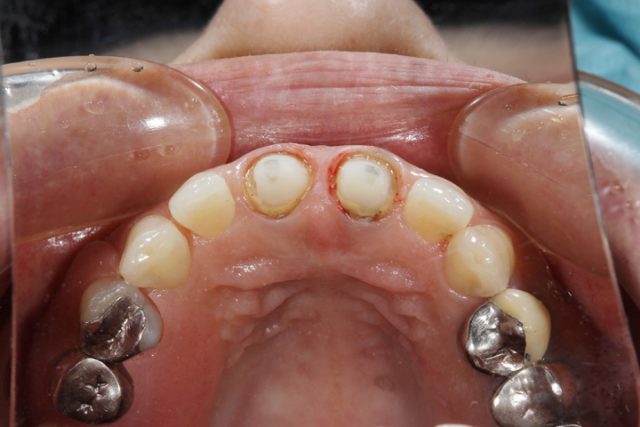

術前の画像から上前歯2本に隙間ができていることがわかります。また、被せ物の付け根も黒ずんでいるのが分かります。

施術中

術中の様子です。被せ物をはずししっかりと土台を形成しなおしていきます。